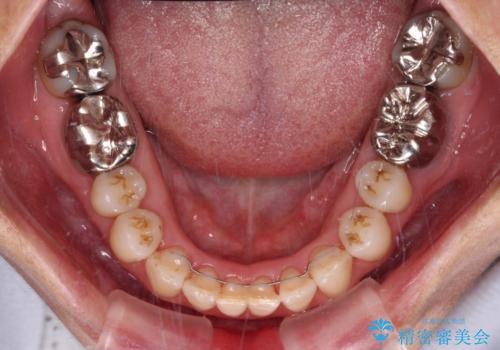

上顎骨の幅が下顎骨よりも小さいので、拡大装置により骨幅を広げて上下関係を改善すると同時にワイヤー矯正で反対咬合の改善を図り、その後インビザラインにて歯並びを整えることとしました。

上顎前歯の矮小歯は矯正治療の途中でオールセラミッククラウンを装着し、左右のバランスを整えることとしました。

急速拡大装置の使用により奥歯の咬み合わせが劇的に変わり、その変化を利用して反対咬合を改善することができました。

治療期間中は奥歯が咬み合わず、食事が取りにくいなどの不都合がありましたが、最終的にはきれいに整えることができました。